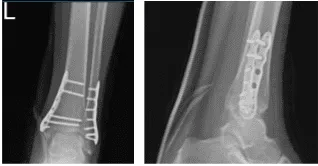

Para entonces, se aconsejó al paciente que realizara la Práctica R.I.C.E (Reposo, Hielo, Compresión y Elevación). Se revisó y monitorizó la radiografía del tobillo izquierdo durante 32 semanas postoperatoria, mostrando fracturas quirúrgicamente tratadas en el peroné distal y la maléola medial.

Radiografía del tobillo izquierdo completada 3 o más visitas-4 semanas después de la operación